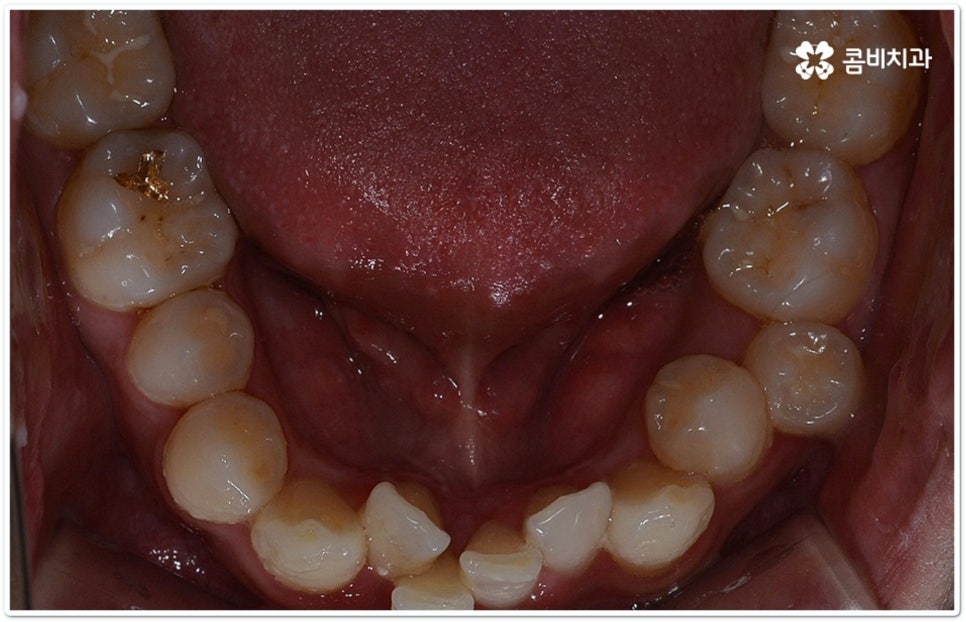

출처 아카이브 열기교정 치료는 교합이 잘 맞지 않거나 치열이 삐뚤어졌을 때 장치를 치아에 부착하여 기능성과 심미성을 회복할 수 있도록 해 주는 것으로 최근들어 관련 기술과 장치 등이 많이 발전하면서 보다 대중화되고 있습니다. 그러면서 예전에 교정을 하고 싶었다가도 오래 걸리고 불편하다, 장치가 겉으로 드러나는 것이 부담스럽다 등등 여러 가지 이유들로 인해 이를 미뤄두셨던 분들 중 다시 치과를 찾아 문의를 주시는 경우가 늘어나고 있는데요.

만약 치열이 많이 삐뚤어지지 않고 부정교합 정도가 심각한 것이 아니라면, 예를 들어 치아 사이가 약간 벌어져 있거나 조금 덧니로 겹쳐진 케이스라면 해당 부위에만 브라켓을 부착하는 부분 교정을 통해 보다 간편하고 신속하게 치열을 고르게 만들 수 있지만 대부분은 골격적인 원인이 함께 작용하기 때문에 꼼꼼하게 검진을 해 본 후 전체 치아 이동을 통해 교합을 맞춰줄 필요가 있다는 진단 결과가 나오는 경우가 더 많이 있는 거예요.